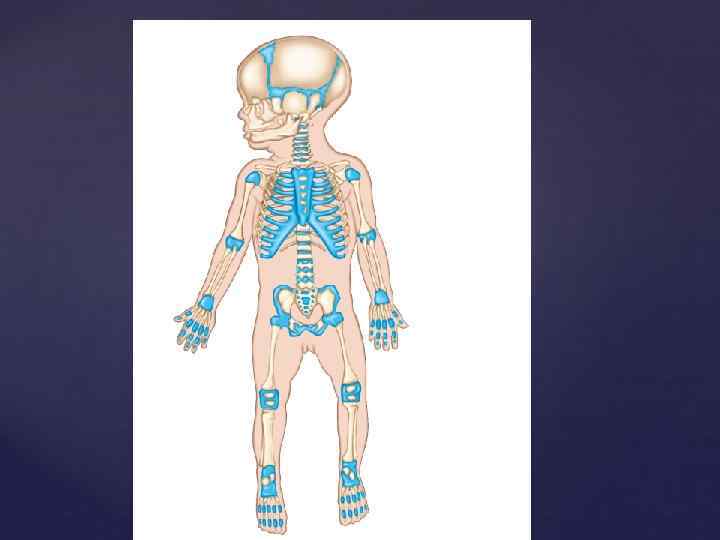

Из всех компонентов опорно-двигательного аппарата естественной рентгеновской конрастностью обладает только КОСТНАЯ ТКАНЬ (из внутренних органов – зубы). До полного окостенения (синостозирования) кости видны как бы фрагментированными из-за наличия ростковых хрящевых зон между участками уже образованной костной ткани. Знания возрастной нормы разввития костей позволяет отличить норм. ренгенологическую картину от травм и заболеваний костей.

Из всех компонентов опорно-двигательного аппарата естественной рентгеновской конрастностью обладает только КОСТНАЯ ТКАНЬ (из внутренних органов – зубы). До полного окостенения (синостозирования) кости видны как бы фрагментированными из-за наличия ростковых хрящевых зон между участками уже образованной костной ткани. Знания возрастной нормы разввития костей позволяет отличить норм. ренгенологическую картину от травм и заболеваний костей.

Полное окостенение костей происходит уже после рождения в результате последовательного появления новых центров оссификации, прогрессивно увеличивающихся в размерах и заполняющих костной тканью хрящевые модели апофизов, эпифизов трубчатых костей, тел позвонков, костей запястья и предплюсны. Параллельно с процессом оссификации происходит увеличение размеров костей. Между эпифизом и диафизом длительное время сохраняется метаэпифизарный хрящ, за счет которого кость растет в длину. Полное срастание эпифиза и диафиза (синостозирование) наступает с прекращением роста скелета к 20 – 25 годам.

Полное окостенение костей происходит уже после рождения в результате последовательного появления новых центров оссификации, прогрессивно увеличивающихся в размерах и заполняющих костной тканью хрящевые модели апофизов, эпифизов трубчатых костей, тел позвонков, костей запястья и предплюсны. Параллельно с процессом оссификации происходит увеличение размеров костей. Между эпифизом и диафизом длительное время сохраняется метаэпифизарный хрящ, за счет которого кость растет в длину. Полное срастание эпифиза и диафиза (синостозирование) наступает с прекращением роста скелета к 20 – 25 годам.